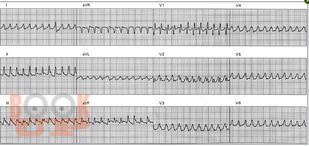

Желудочковые нарушение ритма (ЖНР) в практической деятельности врача достаточно редкая патология, но всегда связана с вопросом риска жизни пациента, поэтому является предметом особой озабоченности врача. В учебном пособии представлены последние достижения в диагностике и лечении желудочковых нарушений ритма, которые часто несут угрозу жизни пациенту. В пособии освещены современные метод диагностики и лечения желудочковой тахикардии при распространенных формах патологии сердца и при редких заболеваниях: синдром Бругады, синдром удлиненного и укороченного QT интервала, аритмогенная дисплазия правого желудочка. Особое внимание уделено внезапной смерти с позиции прогнозирования и профилактики. Учебное пособие будет полезно для практикующих врачей-терапевтов, врачей общей практики и кардиологов.